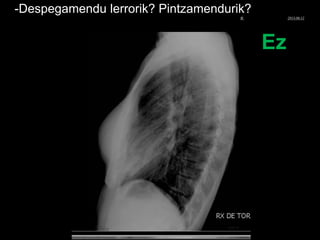

- Despegamendu lerrorik? Pintzamendurik?

Ez

-Despegamendu lerrorik? Pintzamendurik?